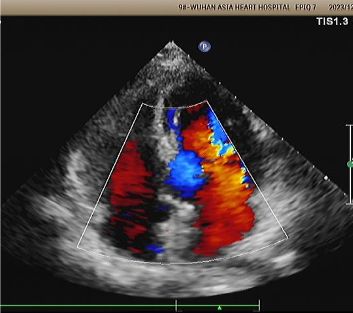

Echo 1-letnie:

No visible disc structures – replaced by 8mm tissue thickening at the septal implant site.

Zero residual shunt (rest or post-Valsalva).

Potwierdzono pełną absorpcję urządzenia.